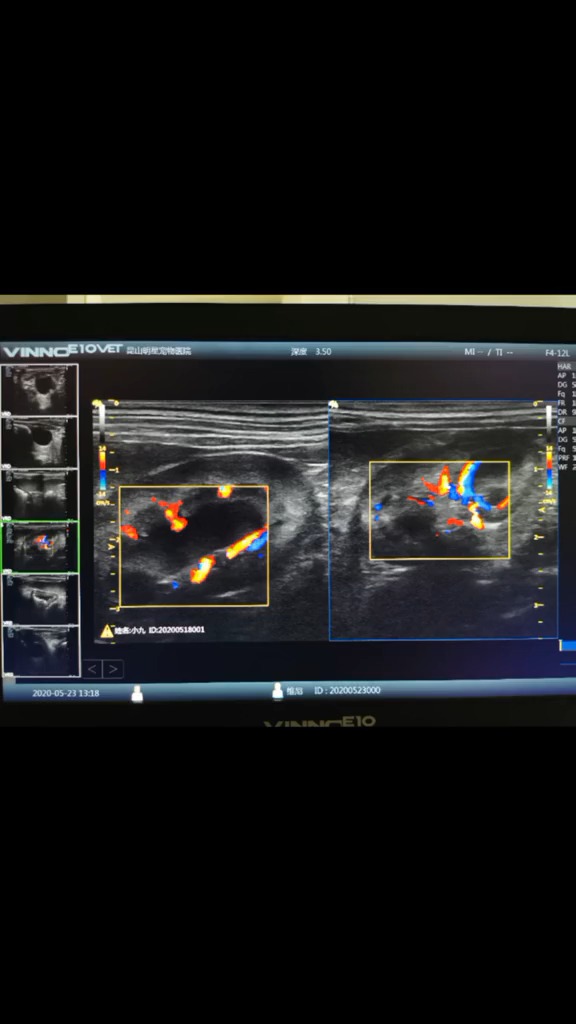

【狗狗胰腺炎伴发肾衰怎么办?】

图片尺寸690x1227